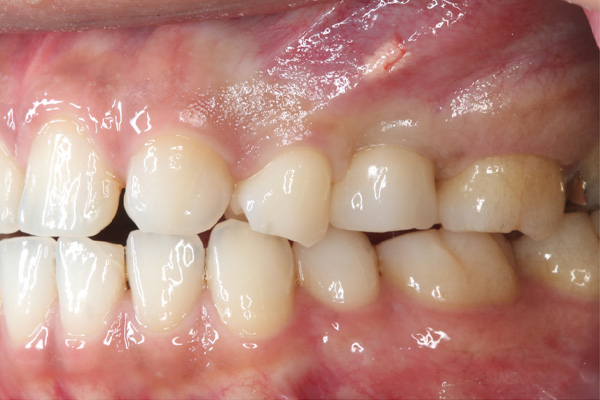

| 年代・性別 | 50代 男性 |

|---|---|

| 主訴 | 右上下の歯が痛い |

| 治療期間 | 約12ヶ月 |

| 費用 | 2,500,000円 |

| 治療内容 | インプラント、骨造成、結合組織移植、セラミック修復 |

| 治療に伴うリスク | インプラント周囲炎 セラミックの破折、脱離 |

*キャンセルポリシーをご一読のうえご予約ください